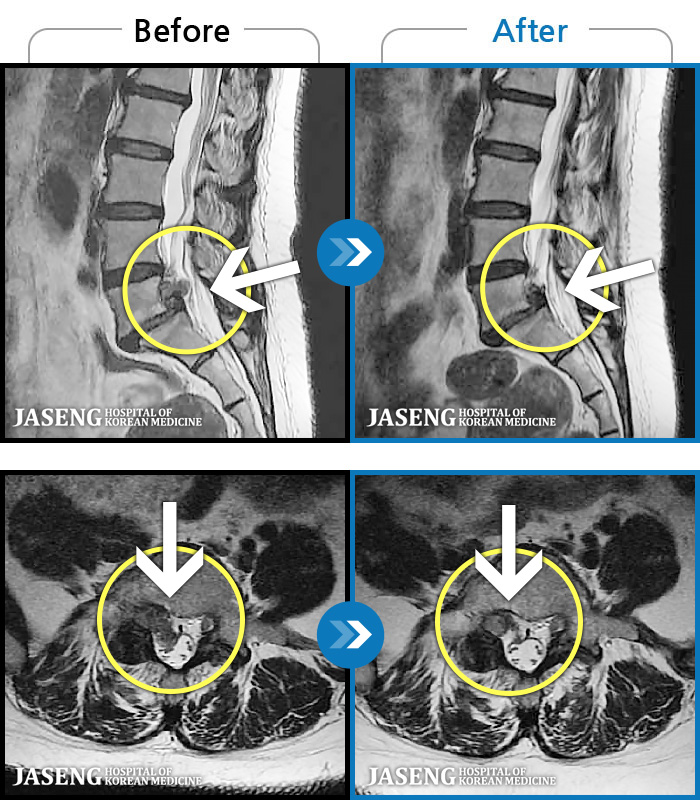

MRI ġ

119 MRI ũ ʸ Ȯϼ.

[Կñ:24.01.30~24.07.09]

[_㸮ũ] ٸ ؼ ɾٴϱ

No.119

ȸ 608

2024.12.24